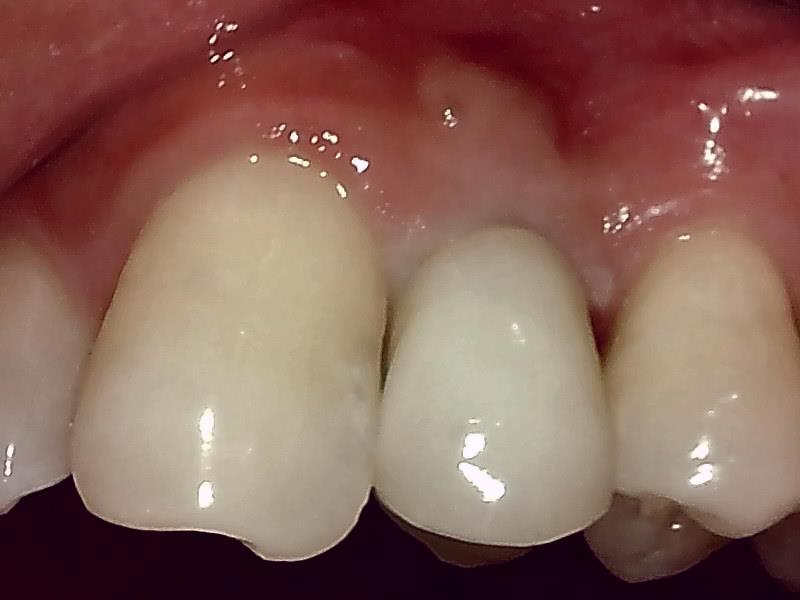

歯肉の整形 (左上)とても綺麗な良い歯肉の状態です。

アバットメント装着 (左上)

(ジルコニアアバットメント)

インプラントの上部構造 (左上)

(ジルコニアセラミッククラウン)